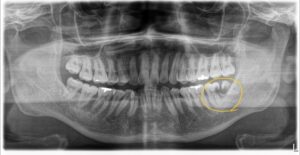

■ レントゲン画像が示す「恐ろしい悲劇」と残酷な現実

このレントゲン画像を見てください。黄色い丸で囲まれた部分が黒く透けている(透過像)のが分かると思います。これが「虫歯」です。

斜めに倒れ込んだ親知らずと、手前の7番の歯の間に食べカスや細菌(プラーク)が溜まり続け、なんと「2本同時に」巨大な虫歯を作ってしまっています。

親知らず自体が虫歯になるのは、正直どうでもいいのです。抜いてしまえば済む話ですから。 本当に恐ろしいのは、「一生使わなければならない大切な7番目の歯の、根っこの深い部分」に巨大な虫歯ができてしまうことです。この部分の虫歯は、外から見ても全く分かりません。

実は、大変残念なことに、今回レントゲンでご紹介したこちらの患者様は、虫歯が歯の根の奥深くまで進行しすぎており、手前の「左下7番」も保存不可能として【抜歯】の診断となってしまいました。